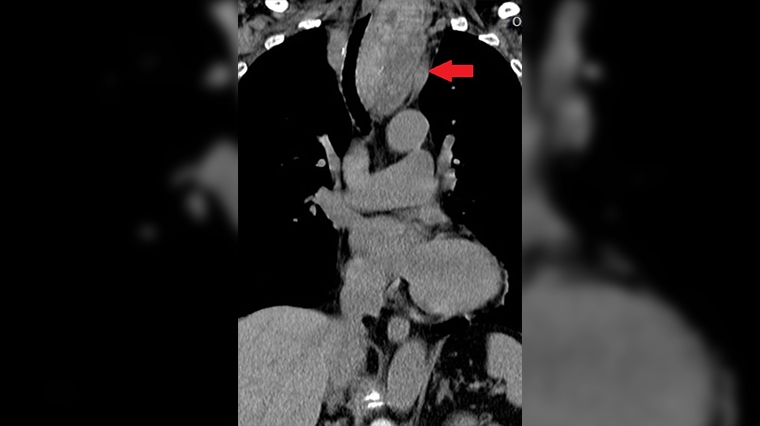

個案黃女士原先是到一般外科評估手術的必要性,後來因結節已經侵犯胸腔,才再轉至胸腔外科就診。收治黃女士的台北慈濟醫院胸腔外科醫師洪嘉聰說,經電腦斷層檢查發現,黃女士的氣管已經被13公分大的結節壓迫偏移至右側,雖然呼吸未受影響,但黃女士仍決定接受手術,以除後患。手術沿著黃女士10年前留下約7公分的頸部傷口切開,將芭樂般大的結節和甲狀腺一併摘除。